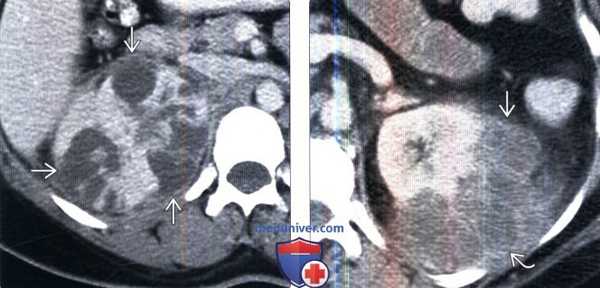

(Слева) КТ с контрастированием, аксиальная проекция: выявлена увеличенная правая почка с множественными скоплениями жидкости неправильной формы, не накапливающими контраст. Данные признаки характерны для многоочаговых абсцессов.

(Справа) КТ с контрастированием, аксиальная проекция: выявлены многокамерные абсцессы почки с ободковым контрастированием и абсцессы околопочечного пространства.